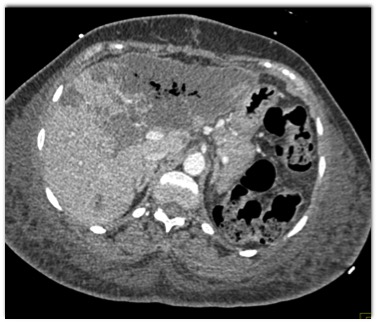

In this patient post recent Whipples procedure the best diagnosis is?

CTisus Quiz   CTisus Quiz

liver abscess

liver infarction

fatty infiltration of the liver

tumor recurrence in the liver